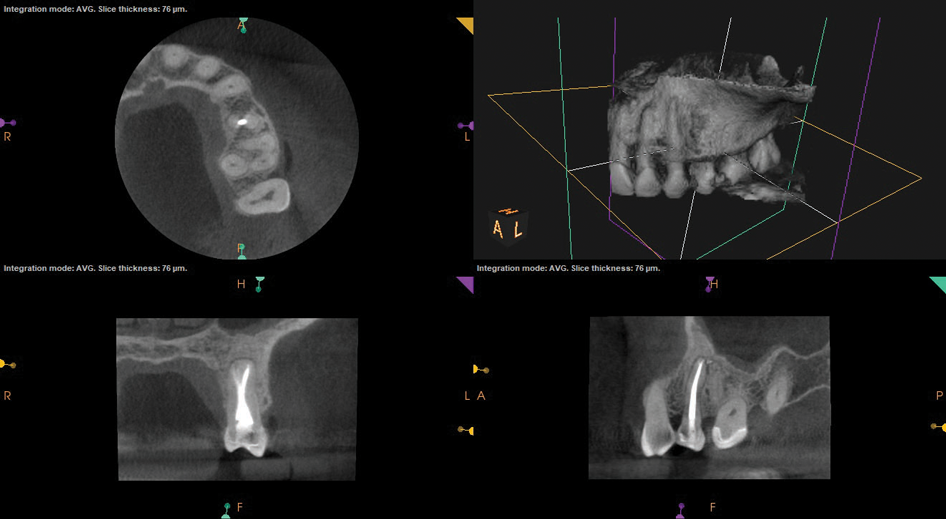

Periapical and CBCT imaging confirmed the presence of apical pathology, as well as a dramatic sinus communication with MSEO (Figure 1 and Figure 2). The diagnosis for tooth No. 13 was pulpal necrosis with asymptomatic apical periodontitis. NSRCT was completed (Figure 3). At the patient's 1-year follow-up appointment, tooth No. 13 remained asymptomatic, her sinusitis was resolved, and complete radiographic healing of both periapical pathology and the MSEO was noted (Figure 4).

Fig 2. Preoperative CBCT. Note periapical pathology associated with tooth No. 13 communicating with the adjacent maxillary sinus along with associated mucositis.

Figure 2